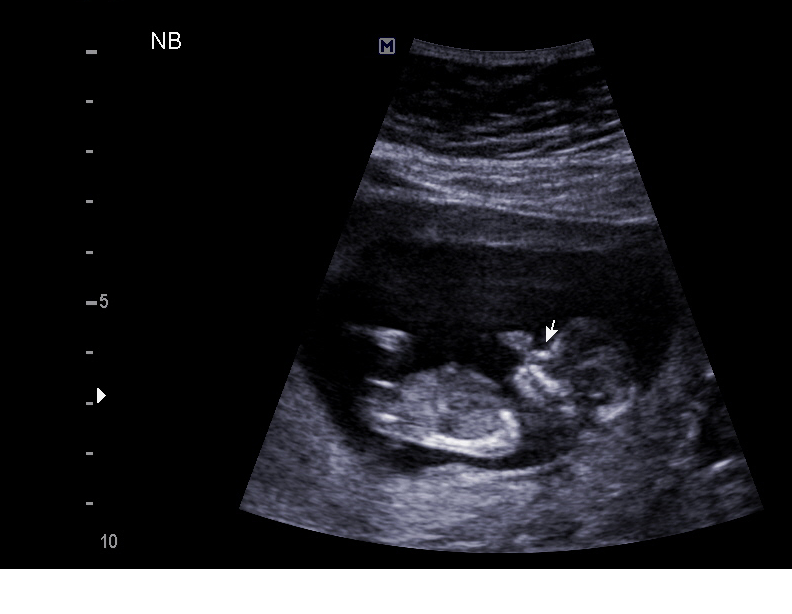

Just got home from my NT scan. All measurements looked good, baby had a heartbeat of 155, and I had blood drawn for the Panorama test.

Doctor also took a look at the baby's heart (we have a history, for those who don't know) which I was NOT expecting. Of course my mind went immediately to the thought that he was only looking because he saw something wrong. BUT he said so far everything looks good! He said he could see crossing vessels and the aorta. Gives me a little peace of mind while I wait two more weeks for CHOP.

He also said it's a boy. I asked "isn't it too early to tell?" but he seemed sure. The doctor, not a tech. I'm still waiting for panorama results to confirm before I tell anyone that, though.